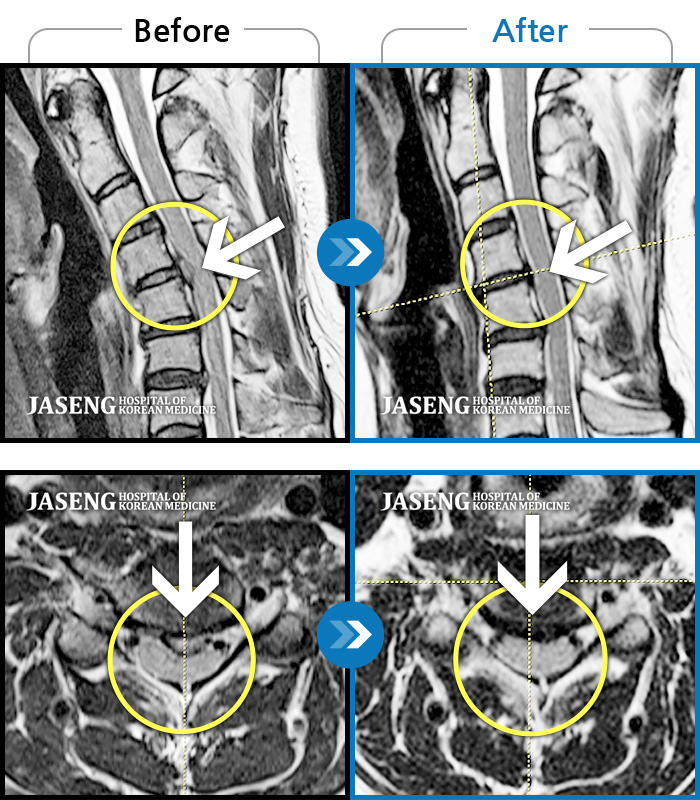

자생 비수술 한방통합치료 후

터진디스크가 흡수된 모습

비수술 치료만으로

터진 디스크 흡수

좌측 목 통증과 좌측 팔저림이 심해서 업무가 힘들었습니다.

2023.07.19 ~ 2024.07.20

Before

After

목 통증이 심해 고개를 돌리기 어려웠습니다

2023.02.13 ~ 2023.04.24